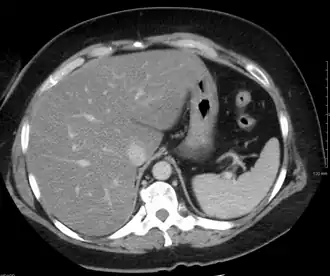

| Tomografia computadorizada de abdômen com fígado gorduroso. | |

As análises de sangue que traduzem o funcionamento do fígado revelam apenas ligeiras alterações inespecíficas. O diagnóstico será feito com exames que permitam visualizar o fígado, como a ecografia ou a tomografia computorizada, que evidenciam um excesso de gordura no fígado. O diagnóstico confirmatório é feito com a realização de uma biopsia hepática (do fígado), sendo positivo caso mais de 10% da sua massa seja gordura, porém esta confirmação não é, geralmente, necessária.[7]